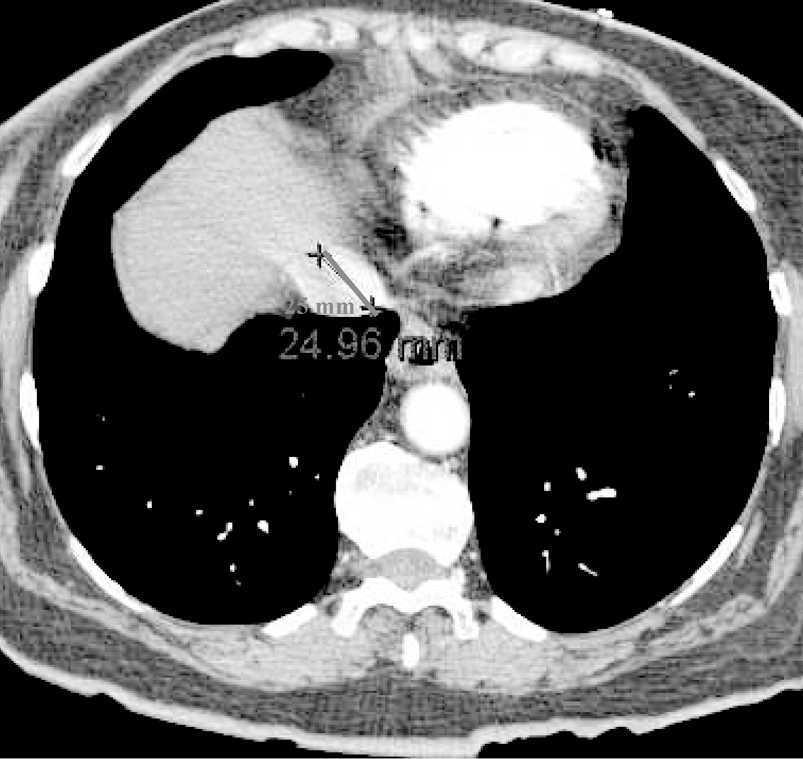

Paciente de 73 años de edad que ingresa en la Unidad de Cuidados Críticos por síncope e hipotensión arterial refractaria a la administración de fluidos intravenosos. En la tomografía axial computarizada (TAC) torácica helicoidal realizada, con protocolo de tromboembolismo pulmonar, se observan signos de embolismo pulmonar extenso con afectación de arterias pulmonares principales y lobares de ambos hemitórax. Igualmente se aprecian signos de sobrecarga ventricular derecha e hipertensión pulmonar. En la figura 1 se observa la dilatación del ventrículo derecho, con índice de diámetro de ventrículo derecho/diámetro de ventrículo izquierdo mayor de 1,5; la flecha indica el abombamiento del septo inter-auricular. En la figura 2 se aprecia, además, reflujo de contraste intravenoso a la vena cava inferior, que se encuentra dilatada. Por tanto, los hallazgos tomográficos podrían servir para valorar de forma indirecta la sobrecarga aguda del ventrículo derecho, secundaria a un tromboembolismo pulmonar.

Figura 2.